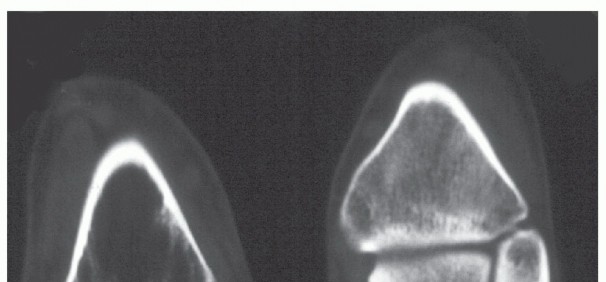

An ankle series of radiographs will reveal the extent of the bone loss, the extent of AVN, and the location of internal fixation hardware in the talus and plafond (FIG 3).

FIG 3 • A,B. Anterior and lateral x-ray of ankle with infected nonunion of talus. The ankle had a draining sinus. The talar body is avascular and the talar head has bone lysis around the two fixation screws. The plafond has erosion and destruction of the cartilage. There is reactive bone on the medial malleolus compatible with infection.*

Computed tomography (CT) scanning will define the fragmentation of the talus and may reveal erosions of the plafond and malleoli compatible with infection.